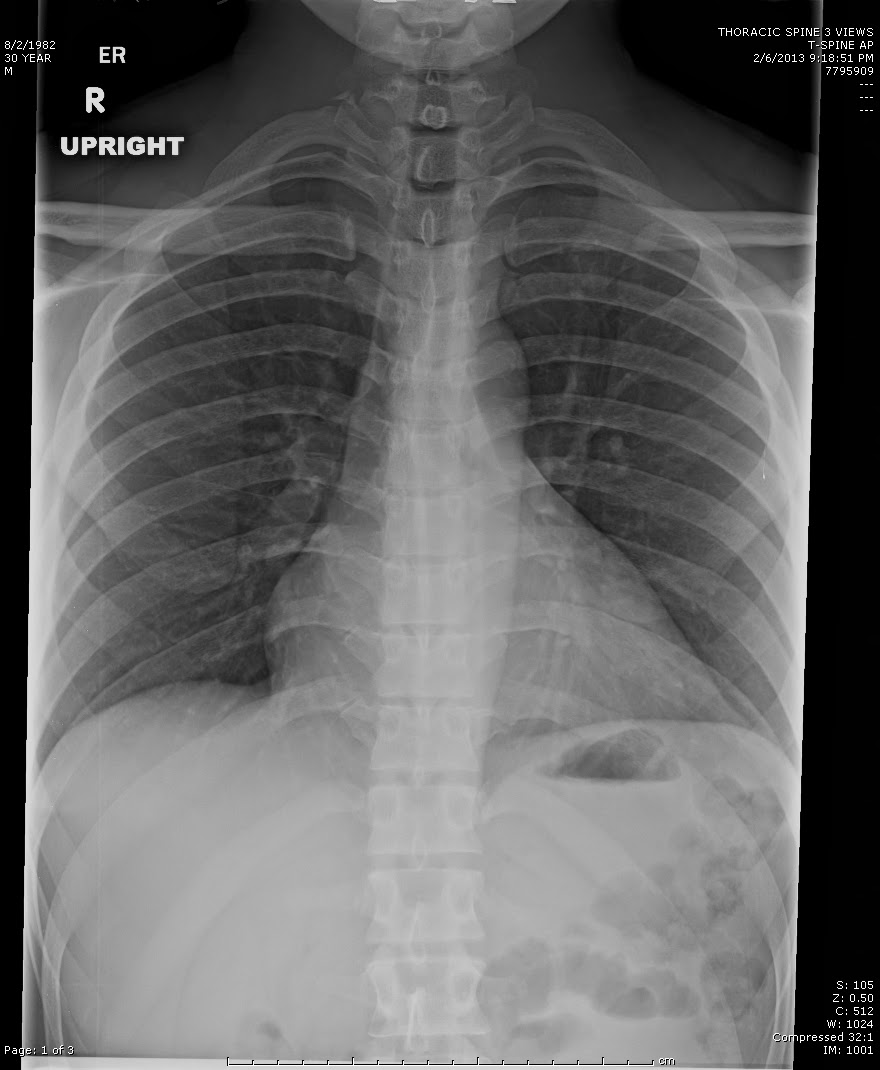

Neumonía

La neumonía es una infección pulmonar que puede ser detectada mediante la tele de tórax. En una radiografía, los signos de neumonía incluyen opacidades en los pulmones, que indican la presencia de inflamación o consolidación de los tejidos pulmonares. Esta condición puede ser grave, especialmente en personas mayores, y su diagnóstico temprano es esencial para iniciar un tratamiento antibiótico adecuado.

Caso Clínico:

Un paciente adulto mayor acudió a consulta con fiebre alta, dificultad para respirar y tos productiva. La tele de tórax reveló una opacidad significativa en el lóbulo inferior del pulmón derecho, lo que confirmó el diagnóstico de neumonía bacteriana. Gracias a la radiografía, se pudo iniciar el tratamiento adecuado de forma rápida, evitando complicaciones mayores.